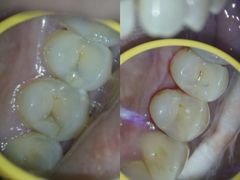

• 同步齿科·数字化正畸种植口腔中心(珠海店)

• -同步齿科·数字化正畸种植口腔中心(珠海店)

dumm_5973 | 24-01-31